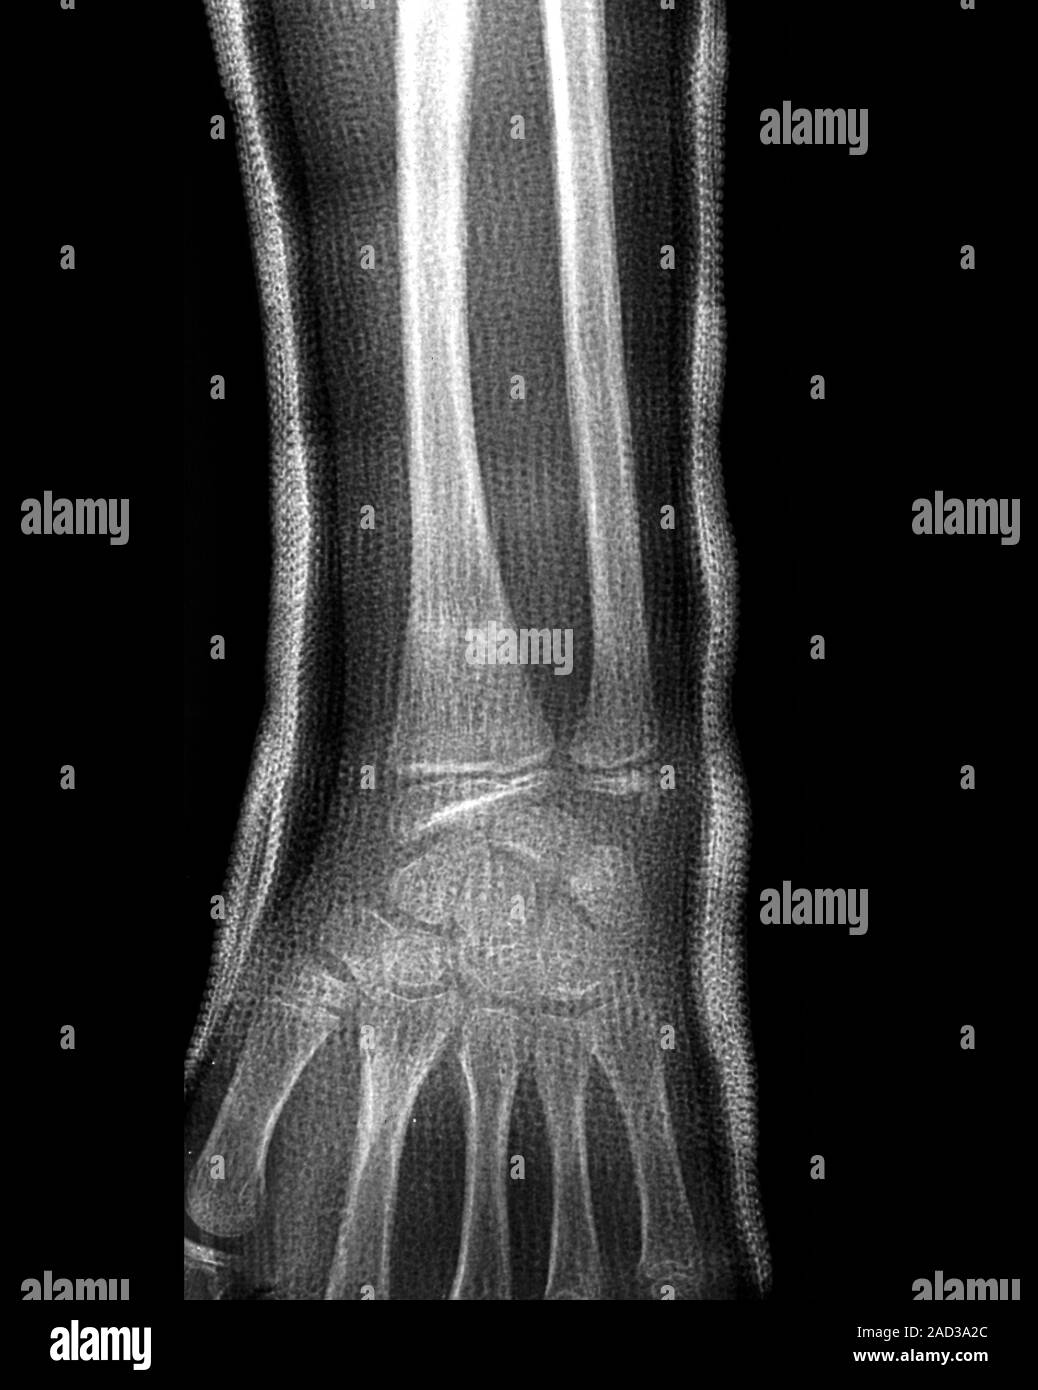

Wrist fracture. Xray of the wrist of a 30yearold patient with a Wrist Fracture X Ray Views In certain circumstances further views are helpful so that. Pa view should be taken with the wrist and elbow at shoulder height. Stable nondisplaced fracture (majority of fractures) if patient has normal xrays but there is a high level of suspicion can. This article provides a comprehensive approach to wrist radiographs, including techniques and common indications for imaging. Distal radius. Wrist Fracture X Ray Views.

Wrist fracture, Xray Stock Image C026/7934 Science Photo Library Wrist Fracture X Ray Views In certain circumstances further views are helpful so that. Pa view should be taken with the wrist and elbow at shoulder height. Distal radius fractures are the most common orthopaedic injury and generally result from fall on an. This article provides a comprehensive approach to wrist radiographs, including techniques and common indications for imaging. Stable nondisplaced fracture (majority of fractures). Wrist Fracture X Ray Views.